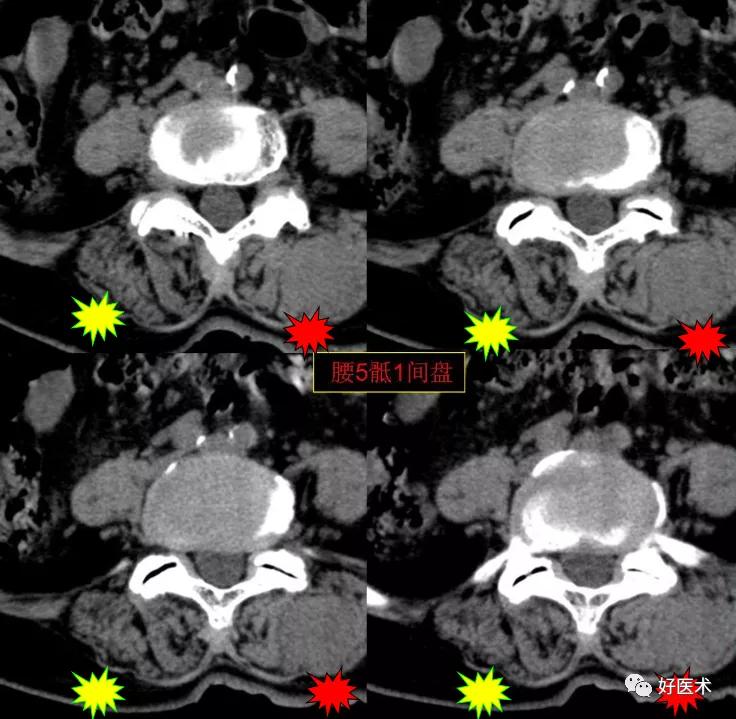

腰5骶1间盘膨隆,双侧椎小关节积气

发现了什么?左侧竖脊肌较右侧明显肿胀饱满, 肌间脂肪间隙消失!!

终于知道了是什么鬼在作乱, 找到了左侧竖脊肌肿胀的元凶:肺癌转移。